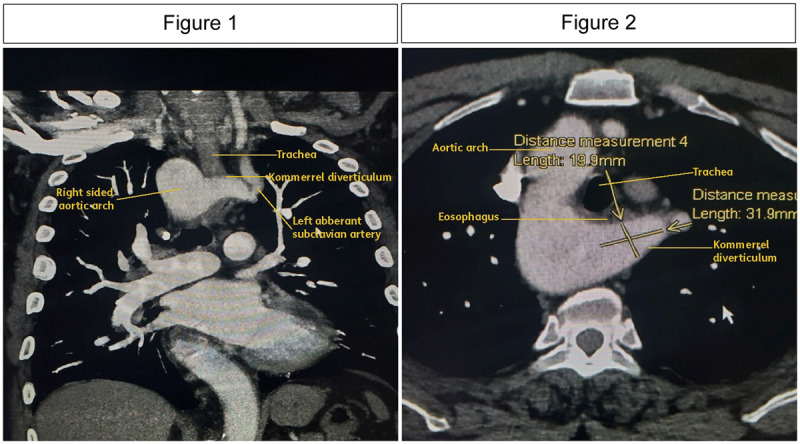

Kommerell's diverticulum (KD) is a rare vascular anomaly characterized by aneurysmal dilation of the descending aorta at the origin of an aberrant subclavian artery, which can occur in either a right- or left-sided aortic arch. Aberrant right subclavian arteries are found in approximately 0.5% to 2% of the population while aberrant left subclavian arteries are less common, occurring in only 0.04% to 0.4%. KD is associated with aberrant subclavian arteries in 60% to 82% of cases. It is often identified incidentally during imaging studies performed for unrelated reasons, which contributes to the limited understanding of its natural progression. However, KD carries significant risks, including a 53% chance of aneurysm rupture and a 19% incidence of aortic dissection. As a result, surgical management is generally recommended. Although no standardized treatment exists, options include thoracic endovascular aortic repair, hybrid procedures, and open repair. Intervention is typically advised when the orifice diameter exceeds 3 cm and depth exceeds 5 cm due to elevated rupture risk. We present a case of incidentally detected KD originating from a right aortic arch with an aberrant left subclavian artery.